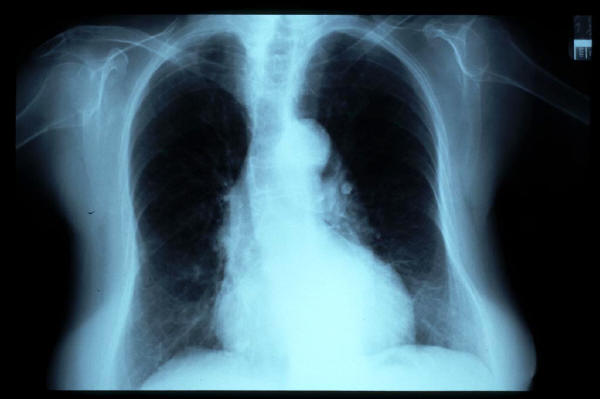

Fibrosis pulmonar. ICC.

Cardiomegalia. ICC.

EAP